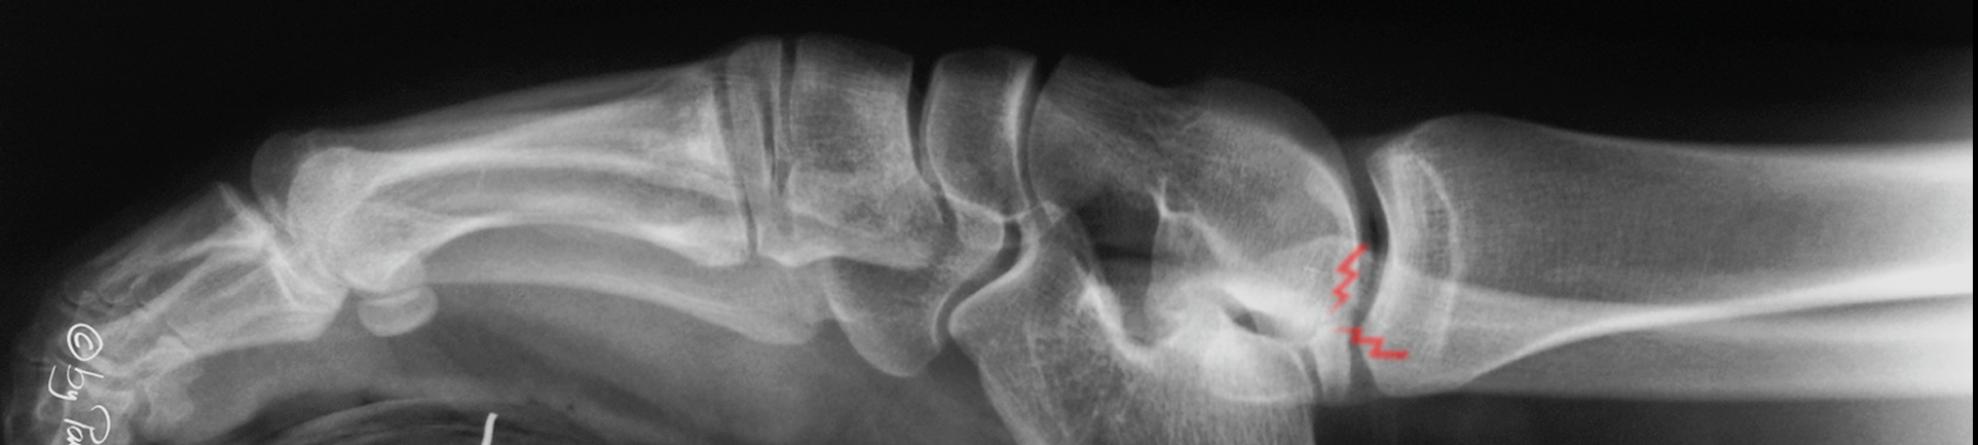

Osteochondral lesion in a patient with sequela of club foot